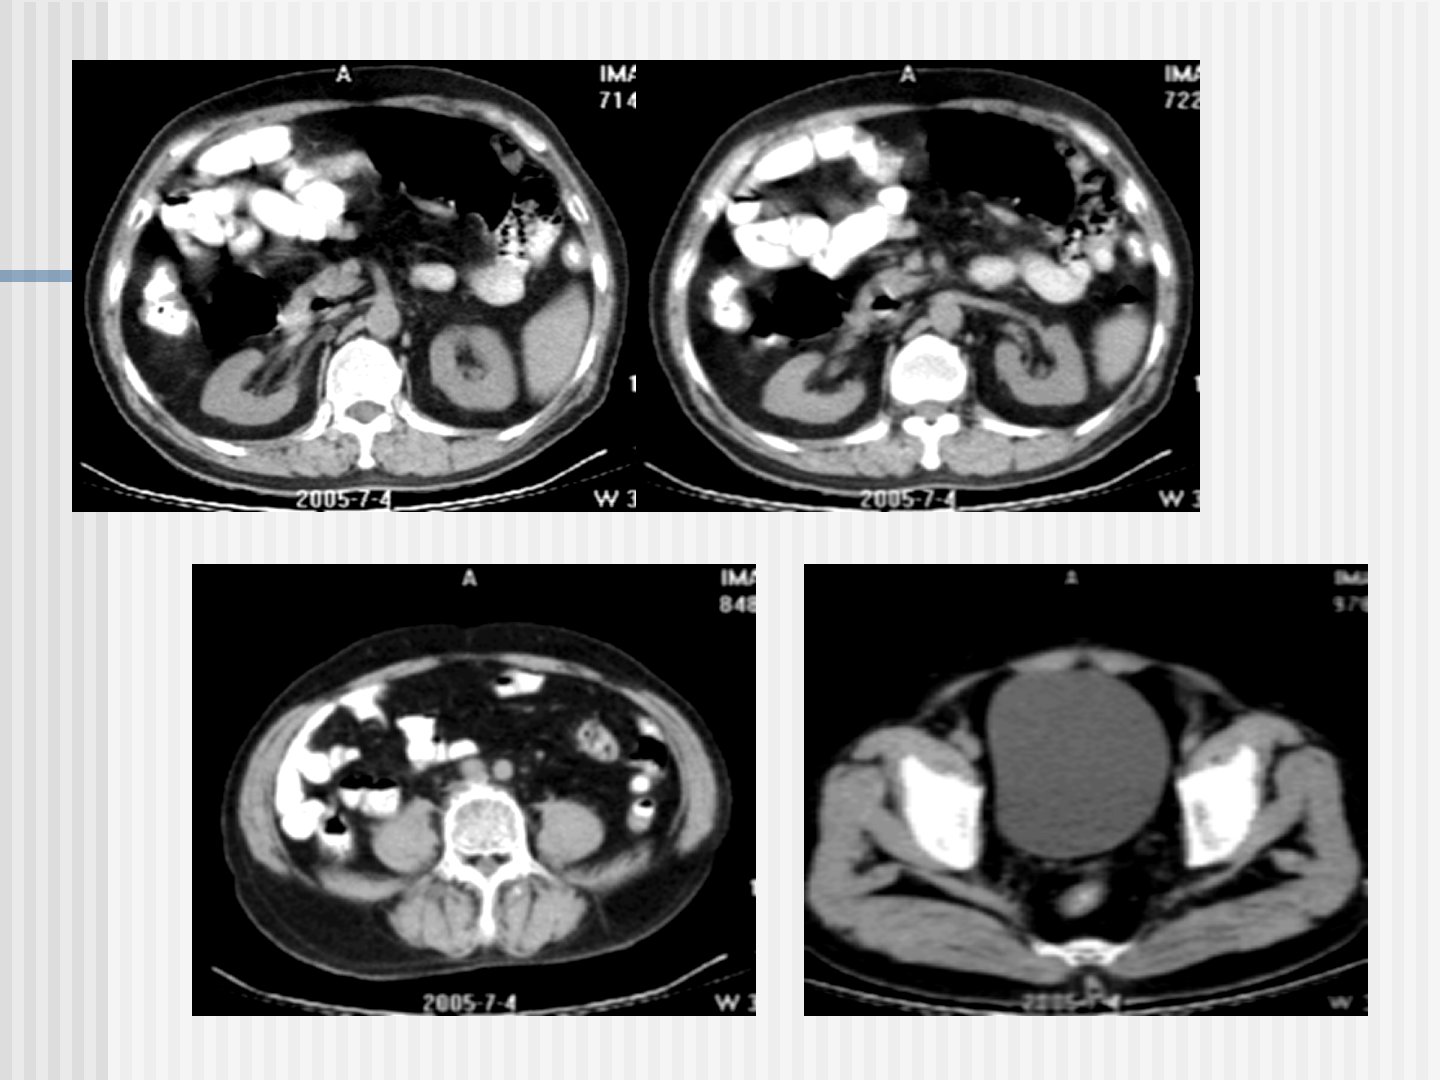

作为医生对肾脏的CT检查与表现总结如下:平扫检查中静脉内快速团注对比剂后进行多期扫描可观察肾皮、髓质强化程度随时间的变化以及肾盂和输尿管的充盈情况。正常肾脏在造影剂皮质髓质排泄期和分泌期会显示特定表现。增强扫描可显示病灶早期强化并能在膀胱腔内对比剂衬托下进一步观察病变形态。CTA检查可无创性显示肾动脉。肾脏平扫显示为脊柱两侧圆形或椭圆形软组织密度边缘光滑。强化表现取决于造影剂用量、注射速度和扫描时间早期肾血管和肾皮质明显强化髓质呈低密度2分钟后髓质强化程度类似或高于皮质。输尿管和膀胱的显示与充盈程度有关。肾脏常见异常密度包括不同肿块如囊性病变、良恶性肿瘤等。肾脏还可能出现大小、形态、位置异常如高密度结石、肿瘤等。输尿管和膀胱也可能出现异常如输尿管扩张积水、膀胱肿块等。此外还存在肾缺如、异位肾等先天异常以及肾结核、肾囊肿等疾病。